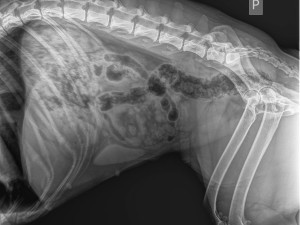

Čtyřmi kulkami trefil fenku Maggie policista, který zasahoval v Praze 10. Podle organizace Nebelvíra, která se případem zabývá, jen štěkala ve tmě a policista bezdůvodně vystřelil. Policie ale naopak tvrdí, že použil služební zbraň, protože na něj pes útočil. Vše ale prověří kontrola.

Jedna kulka zasáhla hrudník, svezla se po hrudní kosti a nezasáhla tak orgány. Další tři pak packu, kterou zřejmě budou muset amputovat.